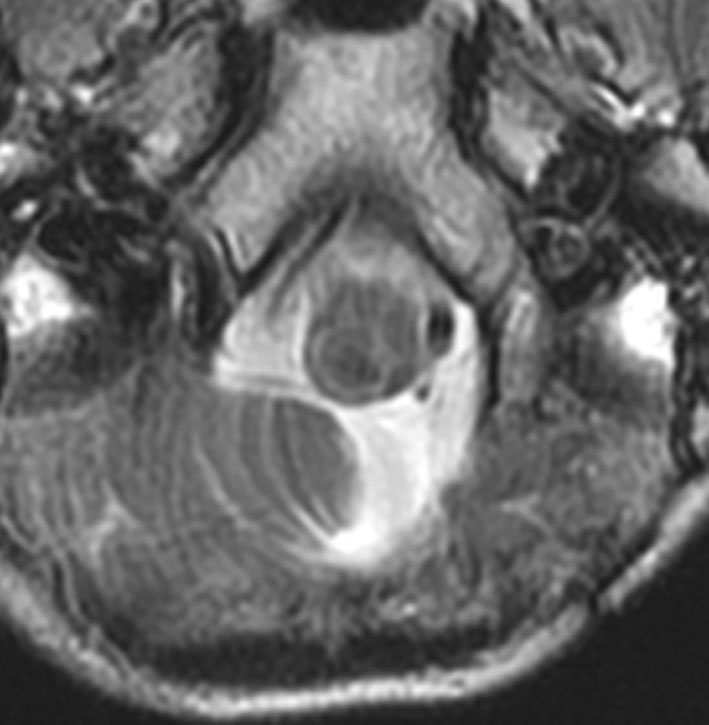

乳児の髄芽腫の治療後の硬膜血管腫

生後8ヶ月で髄芽腫を発症して,手術後に8コースの化学療法して,残存腫瘍があったために2歳半で脳脊髄照射18グレイと後頭窩局所照射21.6グレイをしました。放射線治療後2年で見つかった左前頭部腫瘍です。てっきり脳表播種再発かと思いましたが,良性の硬膜血管腫でした。この子は20歳となり再発もなく元気です。幼児期の放射線治療あるいは化学療法は,予想より早期に,珍しい2次腫瘍を誘発することがあると考えたほうがいいのでしょう。この腫瘍の部位には1日線量1.8グレイで18グレイしか照射されていませんでした。